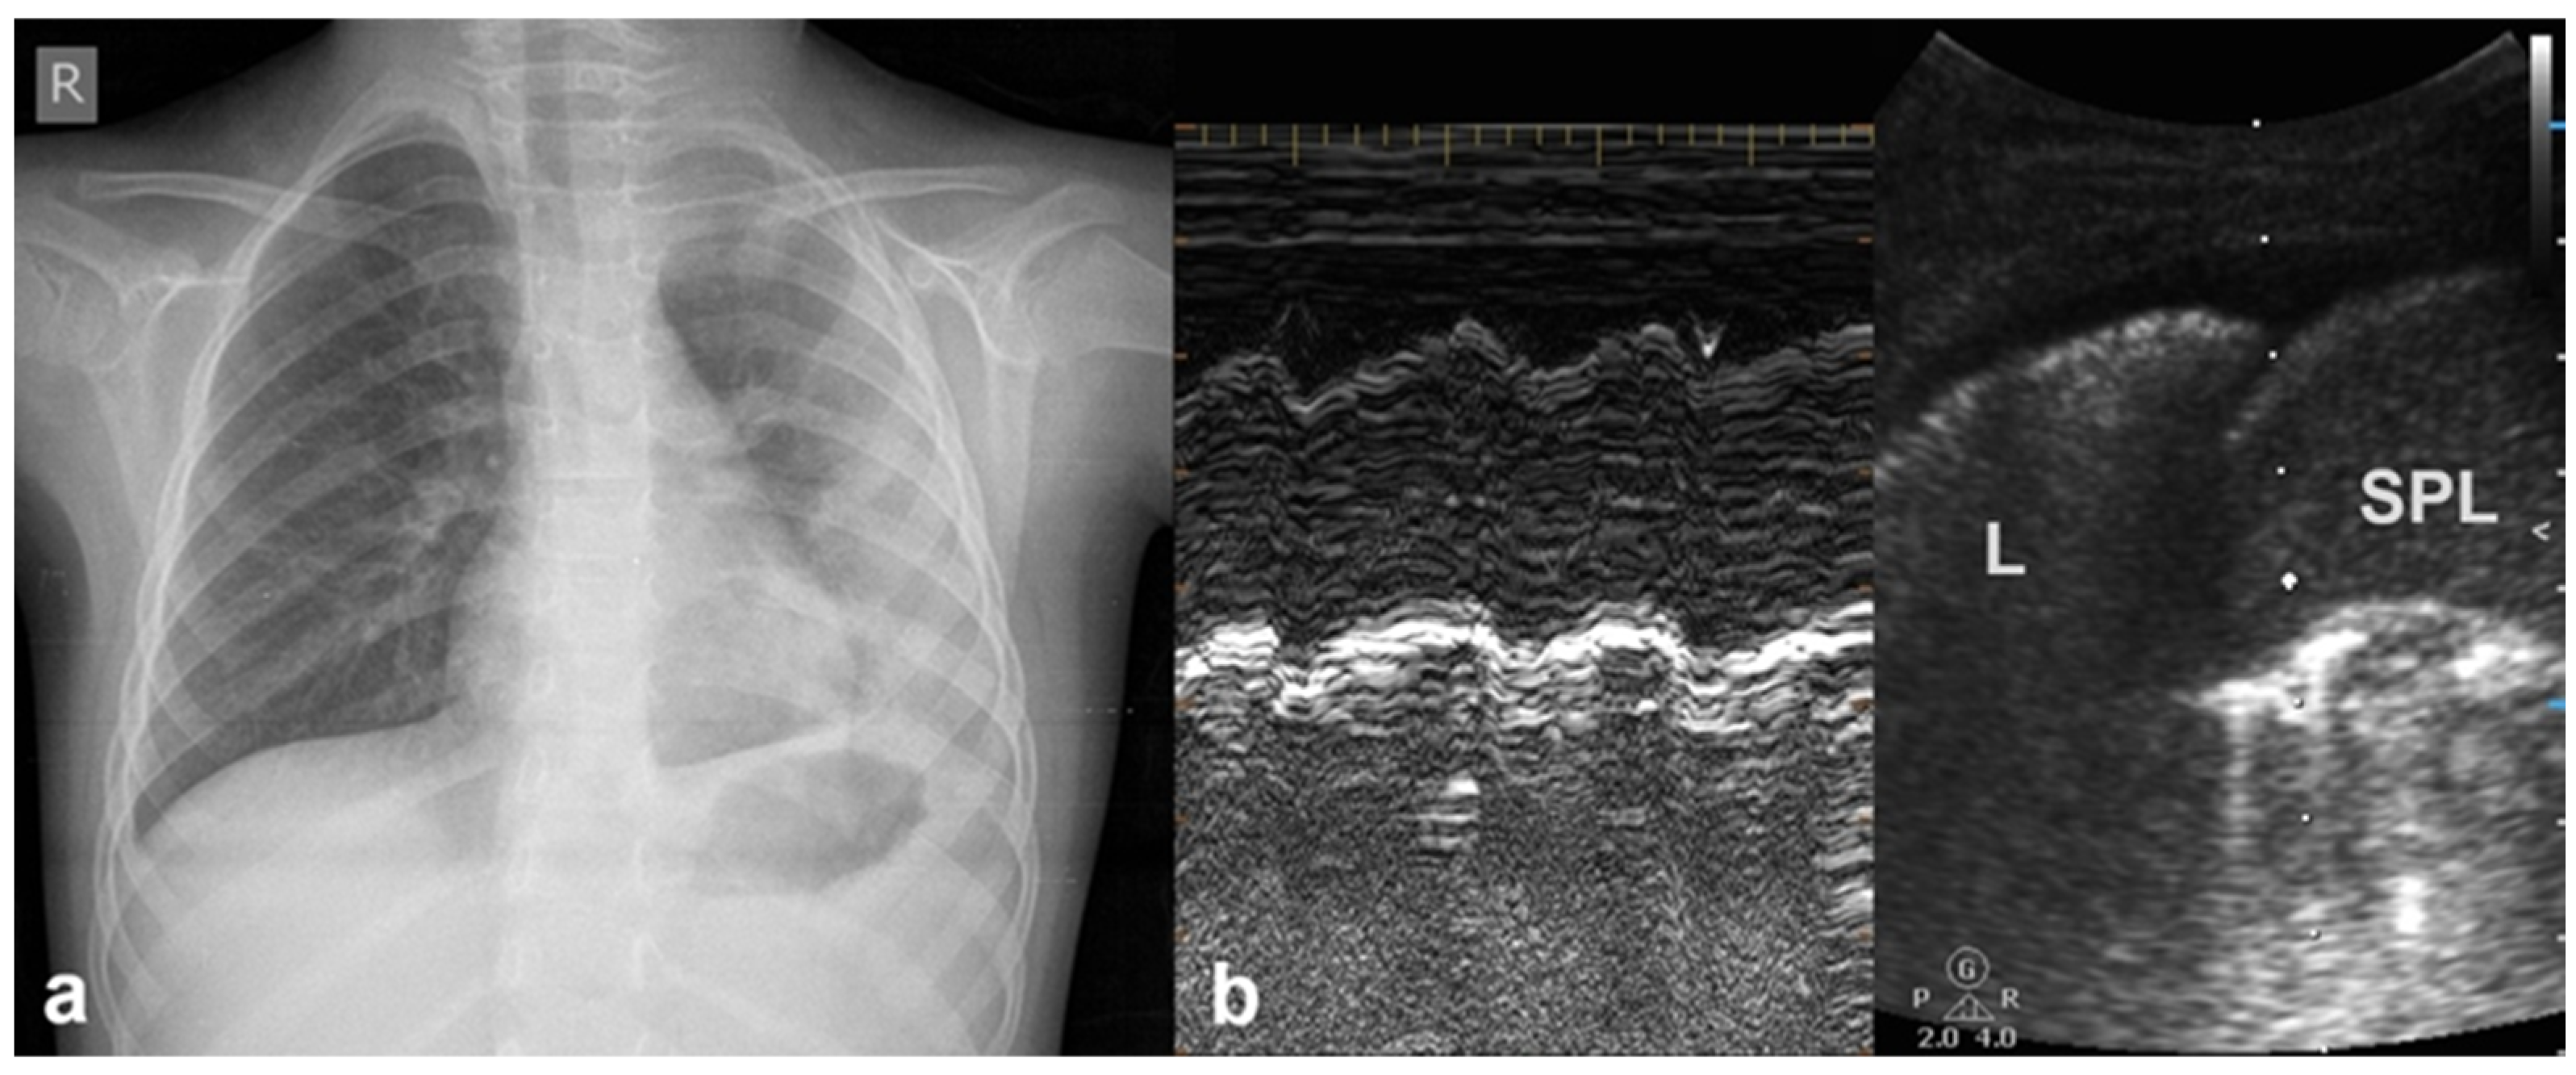

3.1.6. Sinusoid Sign

3.2.10. Pleural Effusion